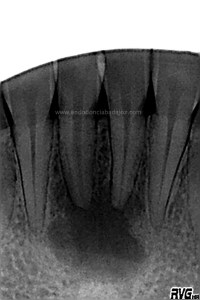

Debido al estudio anteriormente citado, se empezó a hacer el tratamiento de ortodoncia una vez que se comenzó a ver una evolución positiva, con signos claros de regeneración a los 6 meses .

(revisión a los 6 meses)